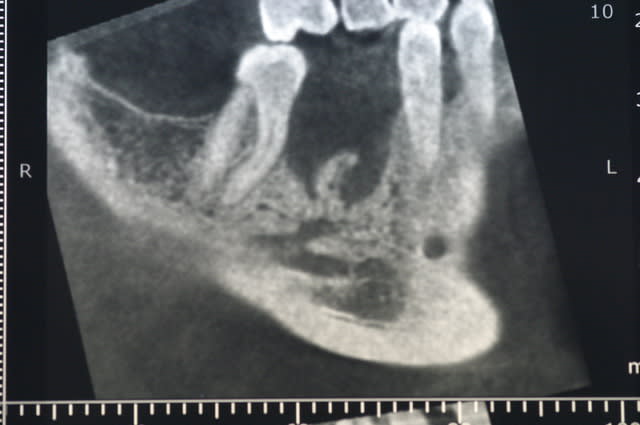

tient pour revenir sur ce que disait Pxav, sur une image comme celle ci, vous passeriez en vestibulaire? c'est vrai qu'il y a de la place, mais je n'ai pas osé...

moi je tenterais pas non plus ce cas là, tout simplement parce que même si tu peux le mettre en vestbulaire, tu n'es plus du tout dans l'axe de la prothese. Alors peut être qu'on peut rattraper avec des pilliers adaptés( et encore), mais à long terme qu'est ce que ça va donner.

sans aucun problème, c'est un bon cas pour commencer.

Par contredans ce genre d'exercice, c'est au spreader, pas au foret.